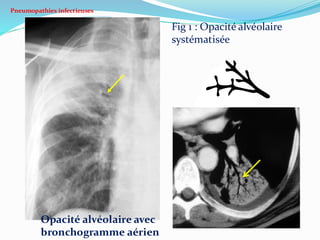

 Pneumonie communautaire: condensation

pulmonaire non rétractile ou opacité alvéolaire (Fig 1).

Pneumopathies infectieuses

Fig 1 : Opacité alvéolaire

systématisée

Opacité alvéolaire avec

bronchogramme aérien